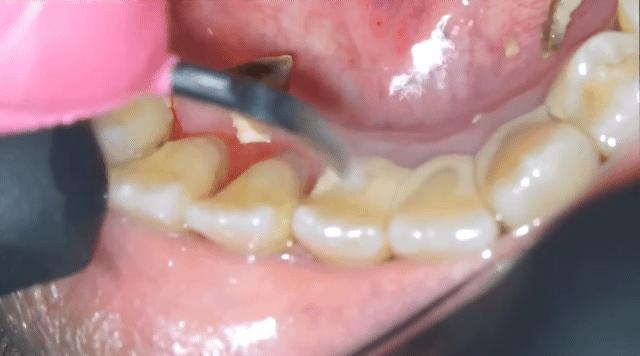

[스크랩] [흥미돋]■ 치과 스케일링 ( 치석 제거)

• 답댓글 작성자야구좋아 | 작성시간 25.03.13 까맣쿤 아니? 아닌 거 같던데! 치석 떼고 나면 잇몸이 부어있어서 그런 욱신거리는 통증?은 조금 있을 수 있어도 치석 많아서 스케일링 할 때 더 아프다는 얘기는 첨 들어봐! 보통 다 못느껴! 치석이 뭉탱이로 떨어지면 그거 막 혀에 닿거나 목구멍에 닿아서 케곅 거리는 사람은 있어...

• 작성자한능검타파 | 작성시간 25.03.13 아 재밌어보이는데... 너무 심하셔서 ㅠ 뿌리가 보일거같아서 안타깝ㅜ

• 작성자박용희 | 작성시간 25.03.13 저정도면 진짜.. 이가 반 정도 빠진만큼 아프겄어

• 작성자촥촥한딸기케이크 | 작성시간 25.03.13 저만큼 쌓일려면 얼마나 안한거야